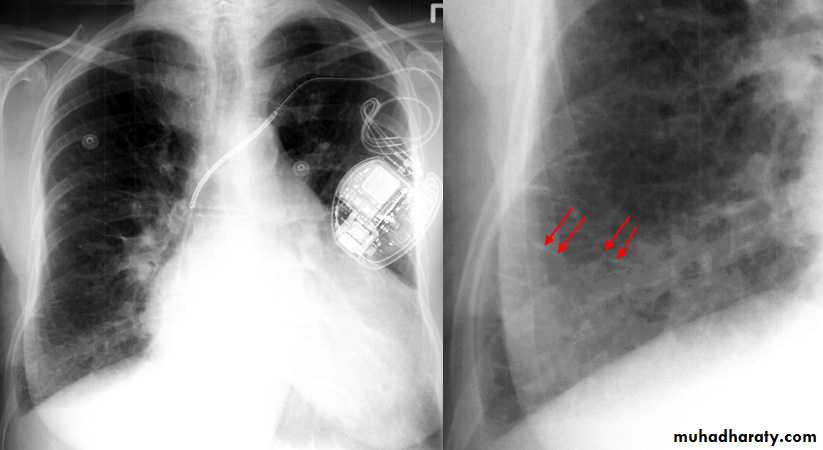

Pneumomediastinum.

Vertical dark (lucent) lines representing air within the mediastinum are usually seen at or above the level of the aortic arch.

On the posteroanterior view (A), these can be seen extending up into the lower cervical soft tissues (arrows).

On the lateral view (B), dark linear air collections can be seen in front of and behind the trachea.